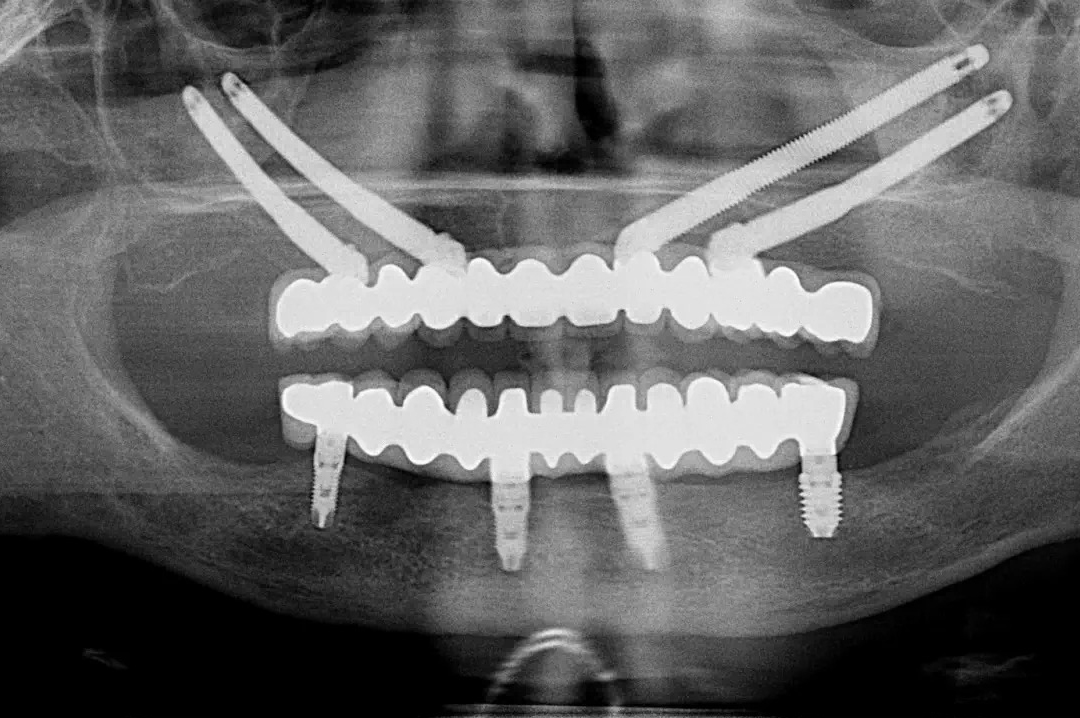

Implantes Cigomáticos

Implantes para pacientes con pérdida ósea severa cuando los injertos no son posibles.

Los implantes cigomáticos se anclan en el hueso cigomático, proporcionando una fijación sólida en casos de atrofia maxilar avanzada.

Son la alternativa ideal cuando el hueso maxilar no permite la colocación de implantes convencionales, evitando cirugías de injertos y permitiendo rehabilitaciones completas.